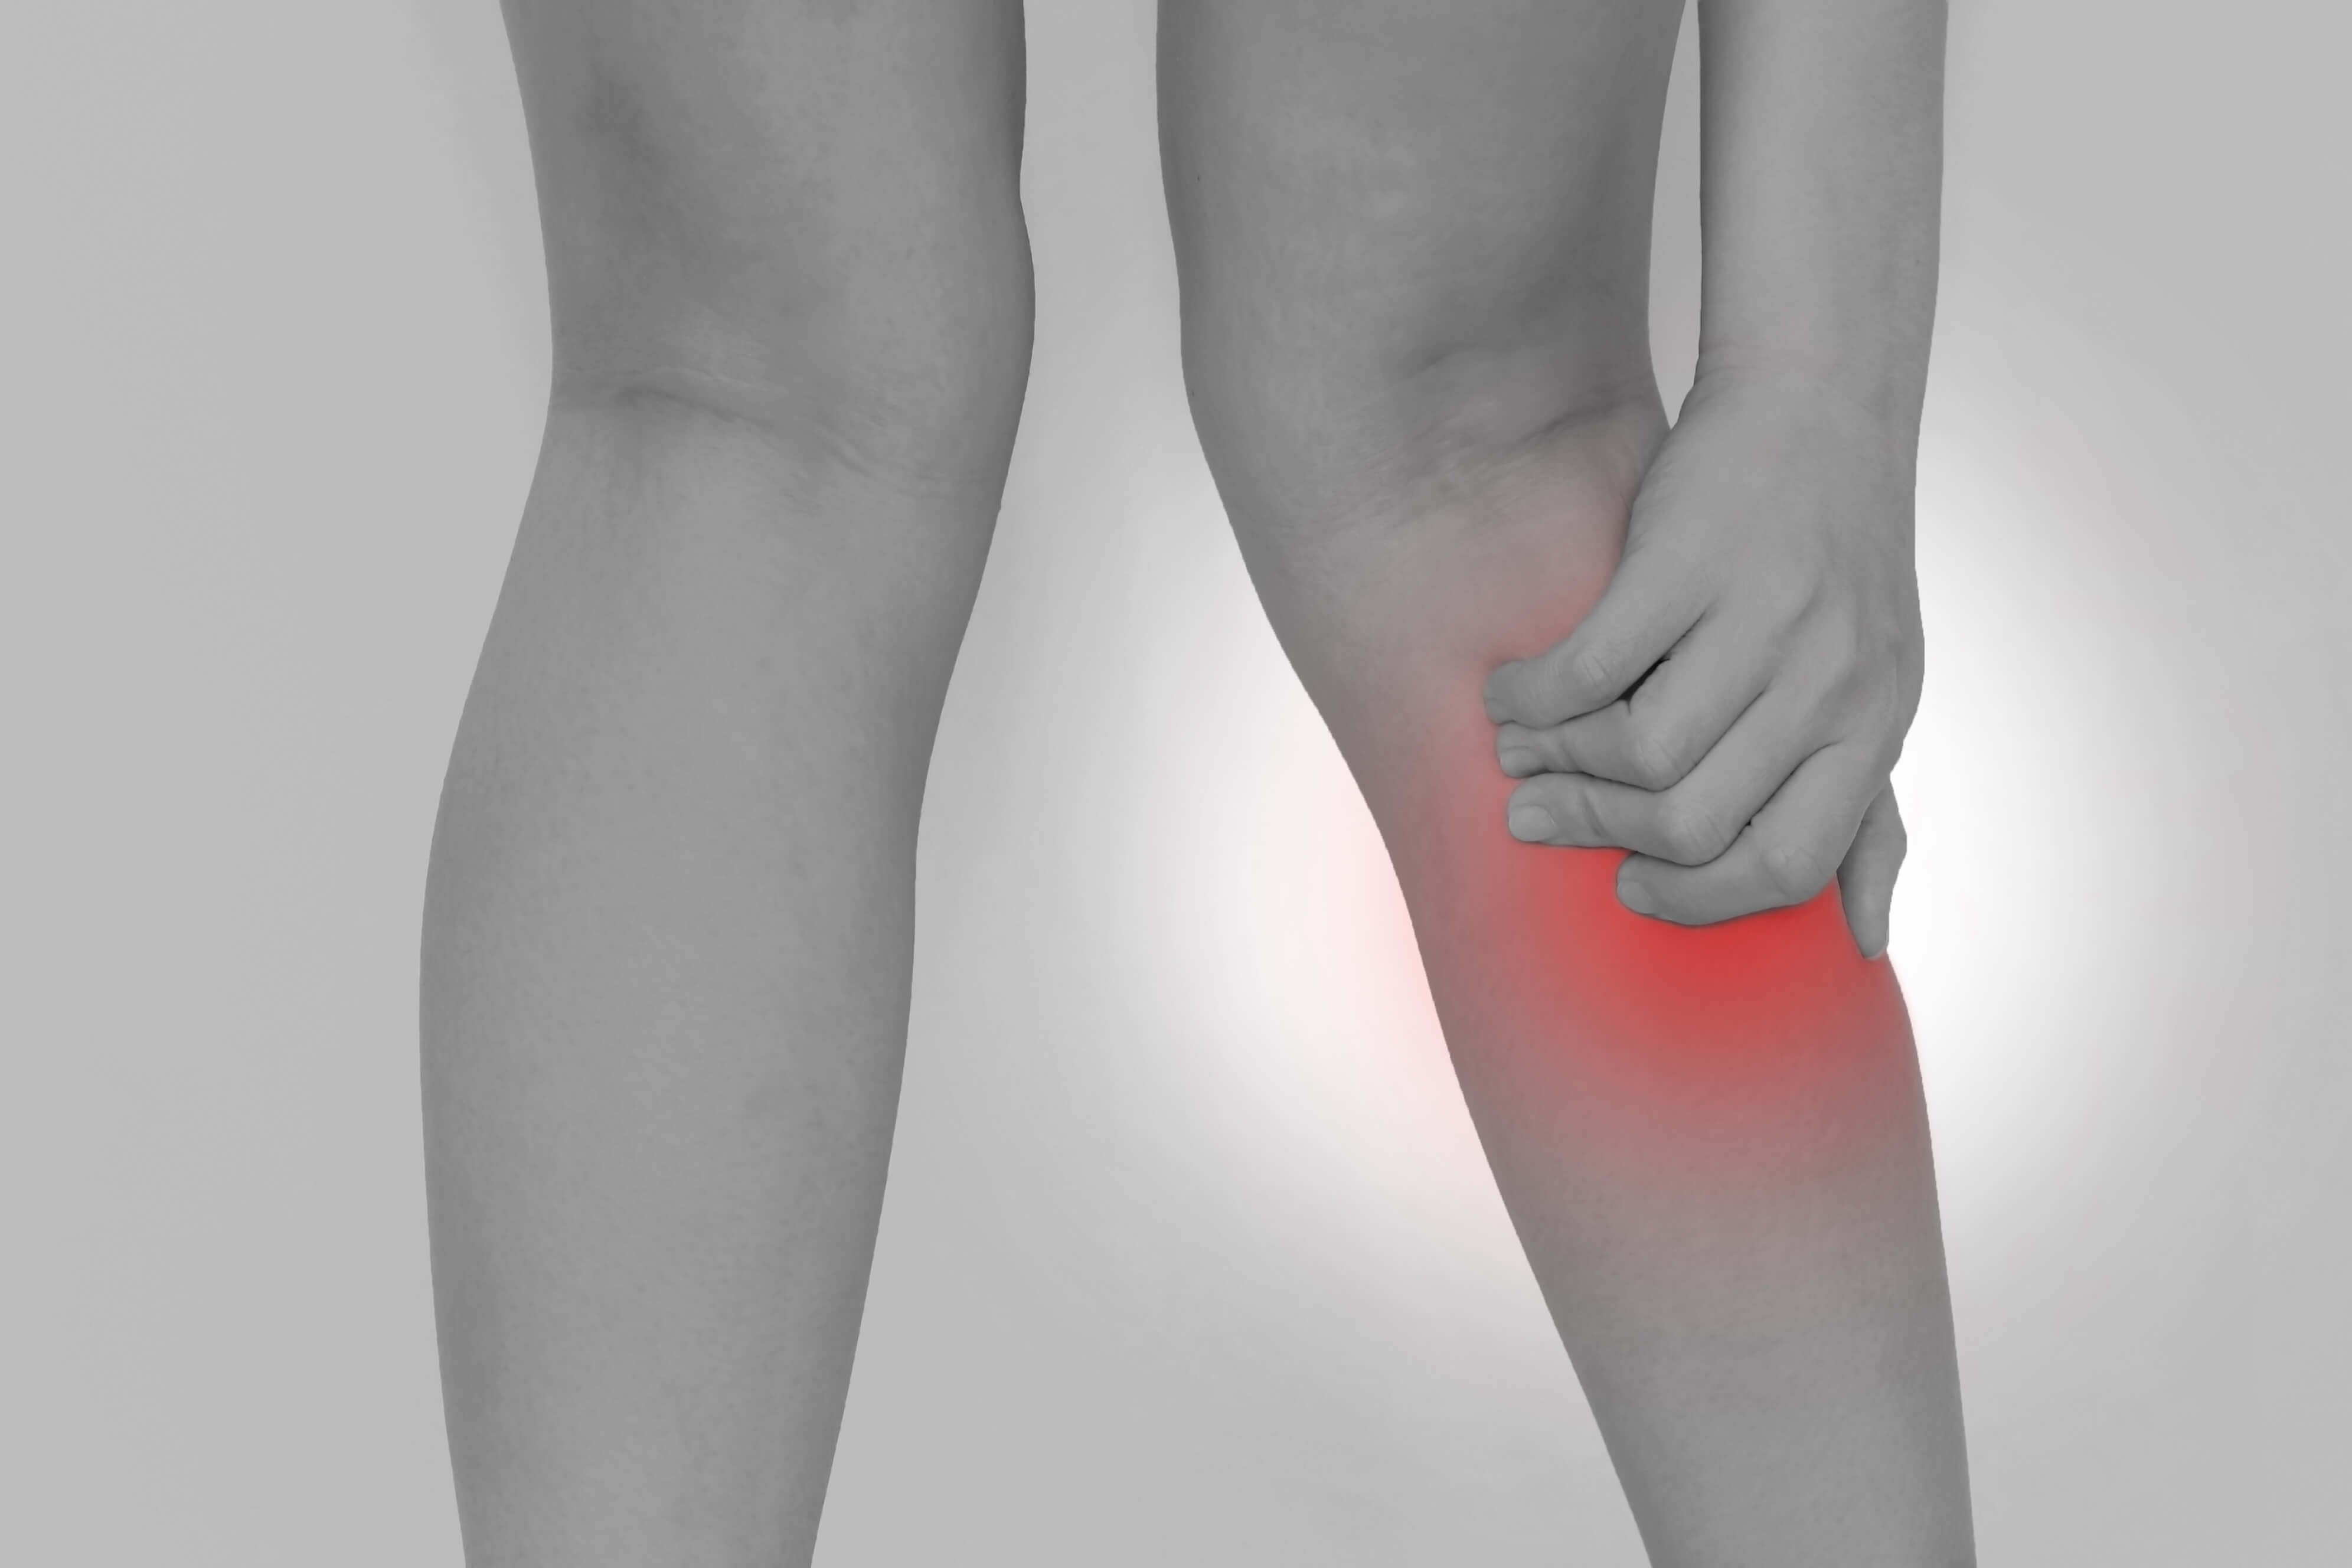

人工膝関節置換術と膝の腫れです。

人工膝関節置換術後を受けると

術後に膝の腫れが出ます。

リハビリを進めていくと

リハビリの影響で膝が腫れます。

リハビリをやりすぎると

膝の腫れが強くでてしまうので

リハビリのやりすぎも要注意です。

そして、

腫れが続いてしまうと

それが痛みに繋がってしまうため

気を付けなければなりません。

というわけで、

膝の腫れというのは、術後しばらく続きます。

どれくらい続くのかと言うと、

およその目安が術後約3か月くらいは

腫れが続くと思ってください。

場合によっては6か月くらい続く人もいます。

腫れが出た場合にはその都度、

膝を冷やしてあげるのが大事です。

膝が腫れたら

膝を労わってあげましょう。

とにかくケアが重要ですよ!